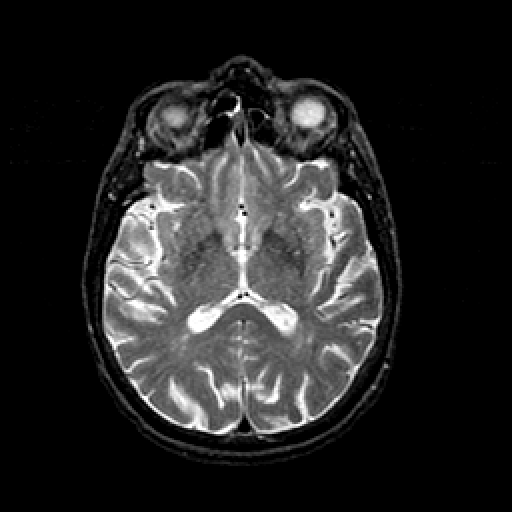

T2-weighted structural MR: Slice 28

Slice 28